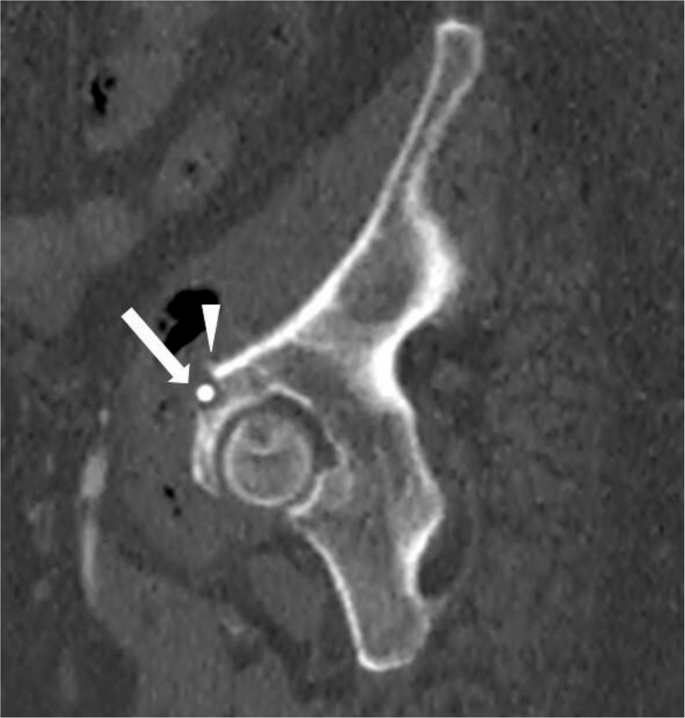

影像学检查显示,一根弯曲的胆道支架从盆腔中部延伸至左下腹,经过髂耻线和髂坐线。即使在单投影X光片上,也能清晰看到支架的远端外侧末端,其末端终止于左髋臼顶部。支架周围局部骨溶解变化表明支架与骨骼有直接接触。X光片未显示髋关节周围有渗出、皮质边界模糊或硬化现象(图1)。增强腹部和盆腔CT显示支架正确放置在胆总管内,而另一根支架则移位至乙状结肠。移位的支架部分位于结肠腔内,其余部分穿透了结肠壁,穿过脂肪层、左髂腰肌筋膜和髂肌,越过髂骨的弓状线,导致髋臼前部出现局部骨质侵蚀,边缘清晰,轮廓平滑(图2)。在支架附近的小范围内观察到单层线性骨膜反应(图2)。在更外围的区域,髂骨上观察到向髋臼前部延伸的硬化改变,以及皮质不规则和小的硬化边缘的侵蚀灶(图3)。

图2

这是盆腔的矢状位增强CT图像(骨窗显示)。可见一根移位的支架导致髋臼前部出现局部骨质侵蚀,边缘清晰,轮廓平滑,侵蚀延伸至髂骨的髓质部分(箭头所示)。在支架附近的小范围内观察到单层线性骨膜反应(箭头所示)

患者的CT检查显示,一根移位的支架穿透了乙状结肠,穿过髂骨弓状线,并局部侵蚀了髋臼前部。支架位置处的左髂腰肌脓肿伴随结肠穿孔。髋臼表面侵蚀、邻近的硬化改变、轻微的线性骨膜反应、皮质完整性以及致密的多房脓肿的存在,强烈提示这是一个慢性病理过程。总体而言,影像学表现与以下假设一致:骨侵蚀最初是由异物造成的压力效应引起的,随后由于伴随的软组织感染引发了炎症反应,进一步促进了骨吸收。她的腿部和髋部疼痛主要由髂腰肌炎症引起。值得注意的是,尽管发生了穿孔,但她的临床表现并不明显,这凸显了高度怀疑的必要性。